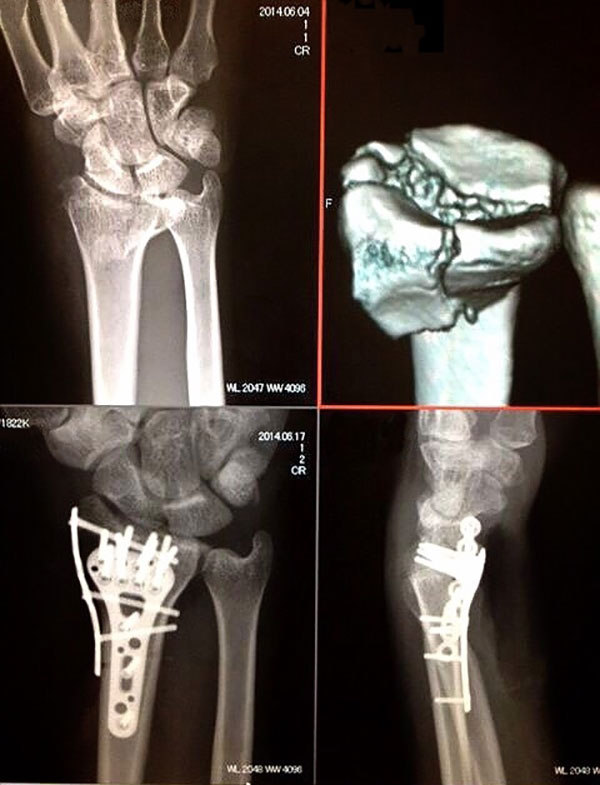

橈骨遠位端骨折 / 舟状骨骨折 など

図3. 橈骨遠位端骨折術前、術後